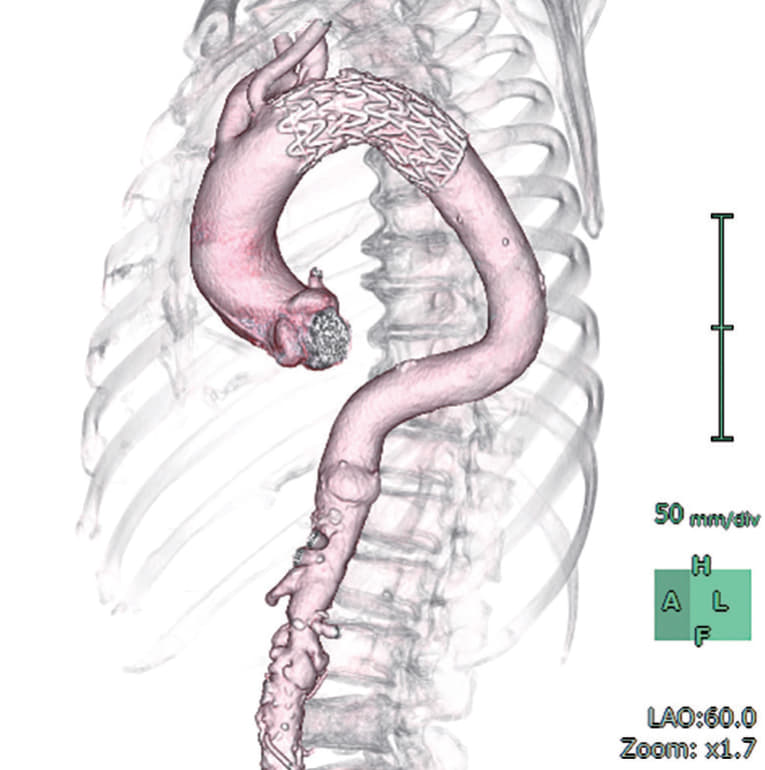

右総大腿動脈に6 Frシースを留置し、アクセスとした 。ラジフォーカスTMガイドワイヤーM**および 5 Frピッグテールカテーテルを上行大動脈まで進行させ、manipulateしたEgoist® EGU35-AC300Q (Arch Curve)ガイドワイヤーを大動脈基部まで到達させた。この時点で透視下にガイドワイヤー押し付けを行い、安定した状態で大弯側に押し付け可能なこと、左室内へ迷入しないことを確認した。22 Frゴア®ドライシール フレックス イントロデューサシースを進行させ、引き続きTAG® コンフォーマブル ステントグラフトTGMR373710Jを適正位置まで進行させた。DSAを施行し、左総頚動脈(LCCA)および左鎖骨下動脈(LSCA)の位置を確認した。ここからは、術者(ドライシールシース固定およびデリバリーカテーテルの操作)・助手(デリバリーカテーテルの固定、ガイドワイヤーの押し付け)の共同操作にて一次・完全展開を行った。ガイドワイヤーを軽く押し付けた状態で、パーシャルアンカバーステントがLCCAに若干かかる位置で一次展開を施行した。ガイドワイヤーの押し付けを加えて、LCCA直下にパーシャルアンカバーステントが位置するように微調整を行った。DSA上のZone 2レベルの小弯側に合わせて、アンギュレーションコントロールダイヤルを回転させて至適な角度に調整した。ガイドワイヤーを押し付けた状態で完全展開を施行した。DSAを施行し、コアキシャルに留置されていること、特に小弯側が至適角度で留置されていることを確認し、この時点でのアンギュレーションコントロールは必要ないと判断した。ガイドワイヤーを用いて、慎重にピッグテールカテーテルを抜去し、引き続き完全展開を施行した。DSAを施行し、エンドリークが無いことを確認した。左上腕動脈よりアクセスし、LSCA根部で造影した。DSA上、明らかなType ll エンドリークを認めず、deployment sleeve部分を含むステントグラフトにてLSCA根部が完全に被覆・閉鎖されていることが確認できた。

結果・術後経過

エンドリークを認めず、初期治療が成功した。術後脳神経学的合併症を認めなかった。術後確認CTにおいてもエンドリークを認めず、軽快退院した。